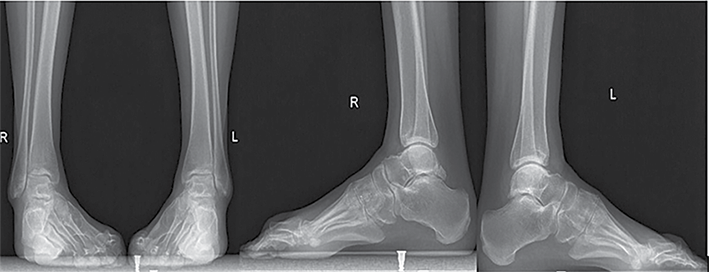

56 m. pacientė atvyko į Lietuvos sveikatos mokslų universiteto ligoninę Kauno klinikas (LSMUL KK) dėl metus trunkančio čiurnos ir pėdos skausmo bei deformacijos. Prieš metus pacientei diagnozuota CMT liga. Rentgeno vaizduose matyti kairės čiurnos cavovarus deformacija, šokikaulio panirimas, čiurnos sąnario artroziniai pakitimai, egzostozės po lateraline kulkšnimi. Kompiuterine tomografija nustatyta III stadijos čiurnos sąnario artrozė ir II stadijos subtalarinio sąnario artrozė. Objektyviai vertinant, pėdos plantarinė fleksija ‒ 20°, dorsifleksija ‒ 5°. Skausmas pagal skausmo skalę (VAS) įvertintas 8 balais (10 ‒ labai stiprus skausmas, 0 – skausmo nėra). Remiantis Europos čiurnos ir pėdos draugijos sukurta funkcijos vertinimo skale (EFAS), čiurnos ir pėdos funkcija įvertinta 4 iš 24 galimų balų (24 balai ‒ gera čiurnos ir pėdos funkcija). Taikant Amerikos pėdos ir čiurnos ortopedų draugijos (AOFAS) čiurnos ir pėdos funkcijos vertinimo sistemą, įvertinimas siekė 23 balus iš 100 galimų (100 balų – gera funkcija). Pacientei atlikta TTC artrodezė intrameduline vinimi, I padikaulio uždaro kampo osteotomija, koreguota padikaulio ašis, ji fiksuota rakinama plokštele ir sraigtais. Po operacijos rekomenduota 2 savaites laikyti koją pakėlus, 15 savaičių dėvėti čiurnos įtvarą, išėmus siūlus, dar 6 savaites dėvėti kompresinę kojinę, 12 savaičių neminti kojos. Po 10 savaičių pacientė turėjo atvykti kontrolinio vizito ir pradėti didinti krūvį. Reabilitacija pradėta praėjus 10 savaičių. Po metų rentgenologinėse nuotraukose matyti čiurnos ir subtalarinio sąnario ankilozė, kaulų ir vinies padėtis gera. Pagal VAS skausmas sumažėjo iki 2 balų, pagal EFAS jis vertinamas 18 balų, pagal AOFAS ‒ 66 balais.

1 pav. Kairės čiurnos ir pėdos tiesinė ir šoninė rentgenogramos prieš operaciją

2 pav. Kairės čiurnos ir pėdos tiesinė ir šoninė rentgenogramos po 6 metų

Po trejų metų pacientė atvyko dėl dešinės čiurnos ir pėdos skausmo, tinimo ir deformacijos. Konservatyvus gydymas buvo neveiksmingas. Vertinant objektyviai: pėdos dorsifleksija ‒ 5°, plantarinė fleksija ‒ 25°, VAS ‒ 8, EFAS – 5, AOFAS – 38 balai. Rentgeno nuotraukose matyti dešinės čiurnos ir pėdos cavovarus deformacija, pradiniai artroziniai čiurnos ir subtalarinio sąnarių pakitimai. Nutarta atlikti dešinio kulnakaulio gumburą lateralizuojančią osteotomiją, subtalarinio sąnario artrodezę sraigtais, Hoke metodika pailginti Achilo sausgyslę ir atlikti plantarinės fascijos fasciotomiją. Nurodyta 8 savaites neminti kojos, 10 savaičių dėvėti čiurnos įtvarą, pašalinus siūlus, dar 6 savaites naudoti kompresinę kojinę. Po 3 savaičių rekomenduota mankštinti koją atliekant pėdos fleksiją ir ekstenziją. Reabilitaciją planuota pradėti po 10 savaičių. Po metų pacientė atvyko dėl išliekančio dešinės čiurnos ir pėdos skausmo, tinimo. Rentgeno nuotraukoje matyti progresuojanti dešinės čiurnos sąnario artrozė ir varus deformacija. Pėdos fleksija ir ekstenzija išliko tokia pati, čiurnos sąnarys nestabilus. Nuspręsta atlikti TTC artrodezę intrameduline vinimi. Praėjus dvejiems metams, rentgenologinėse nuotraukose matyti čiurnos ir subtalarinio sąnario ankilozė, kaulų ir vinies padėtis gera. Pagal VAS skausmas sumažėjo iki 2 balų, pagal EFAS jis vertinamas 21, pagal AOFAS – 71 balu.

3 pav. Dešinės čiurnos ir pėdos tiesinė ir šoninė rentgenogramos prieš operaciją

4 pav. Dešinės čiurnos ir pėdos tiesinė ir šoninė rentgenogramos po dvejų metų